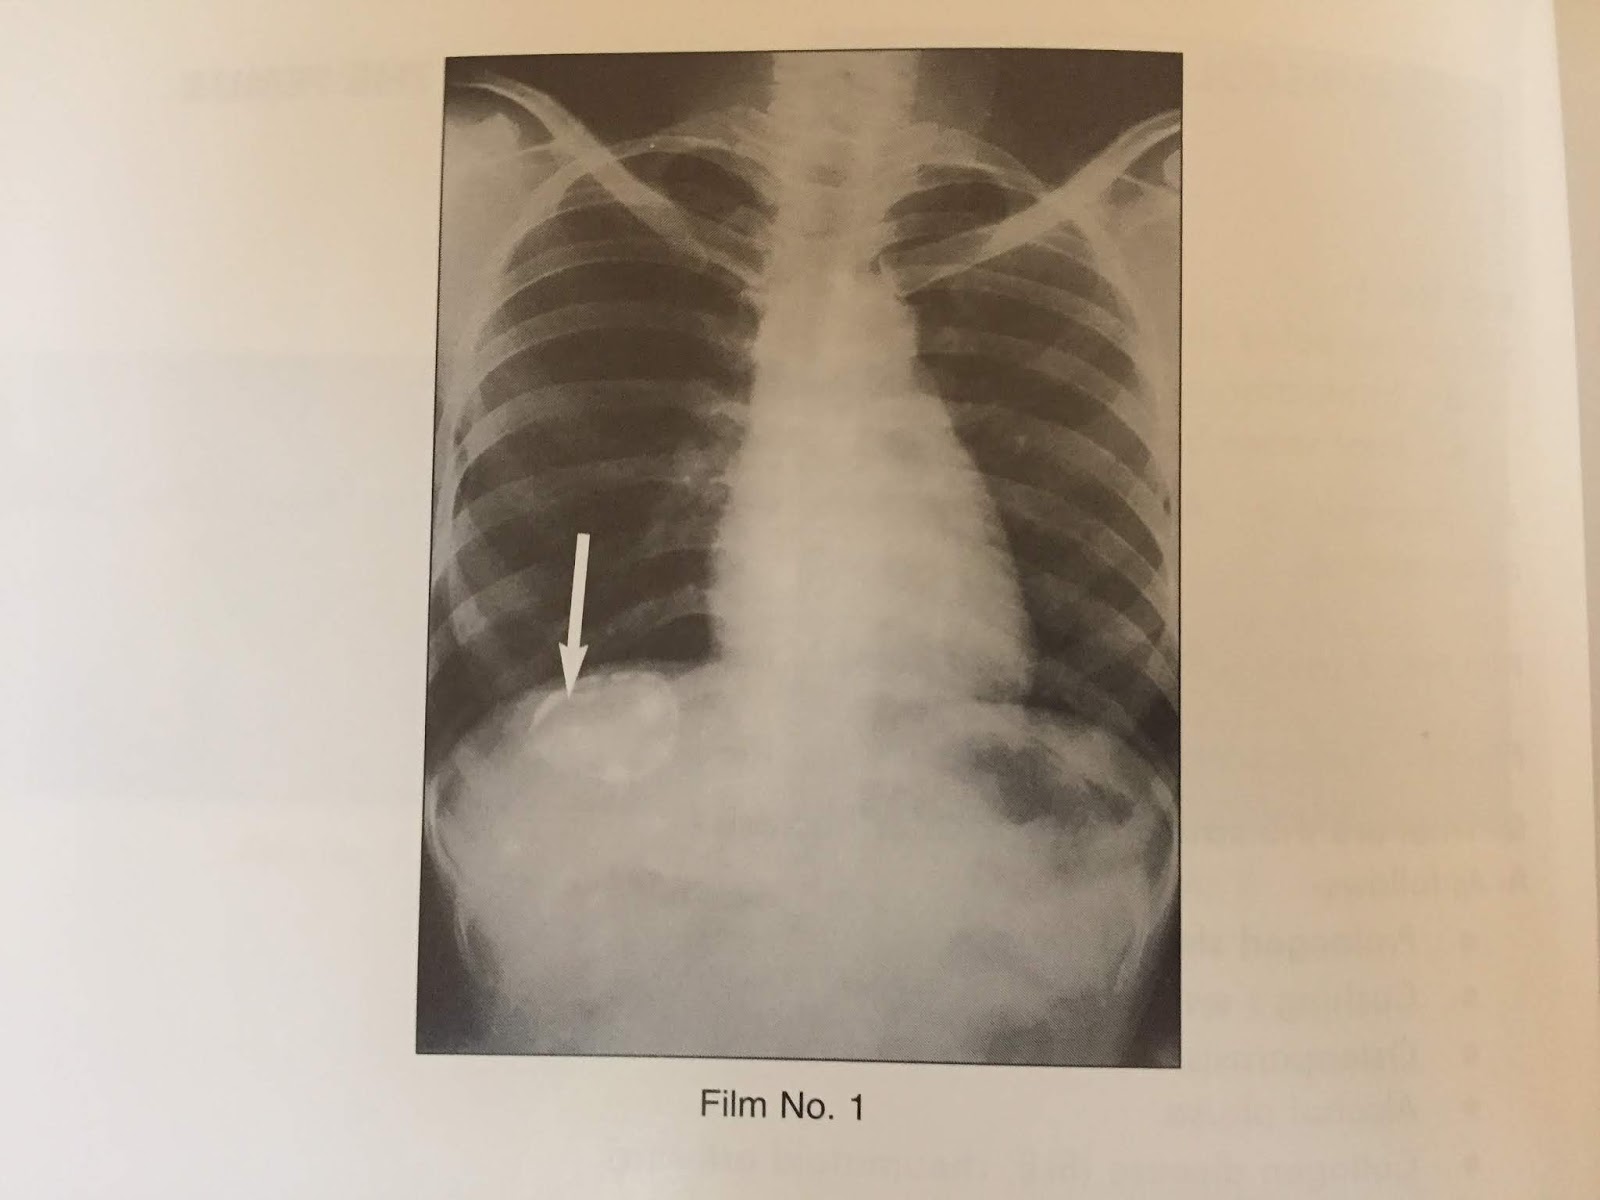

Enlarged liver, Xray Stock Image M170/0433 Science Photo Library

Enlarged liver in straight Xray of abdomen. Download Scientific Diagram Liver In X Ray A liver scan is a specialized radiology procedure used to examine the liver to identify certain conditions or to assess the function of the liver. Cirrhoses) is the common endpoint of a wide variety of chronic liver disease processes which cause hepatocellular necrosis. Mri is used to image blood vessels (without using contrast), ducts, and hepatic tissues. Assessment of liver. Liver In X Ray.

Enlarged liver, Xray Stock Image M170/0435 Science Photo Library Liver In X Ray Assessment of liver size is commonly made on ultrasound or ct, although gross hepatomegaly may be. Liver ultrasonography (us), computed tomography (ct), magnetic resonance imaging (mri) are the primary imaging modalities to diagnose liver lesions. A liver scan is a specialized radiology procedure used to examine the liver to identify certain conditions or to assess the function of the liver.. Liver In X Ray.